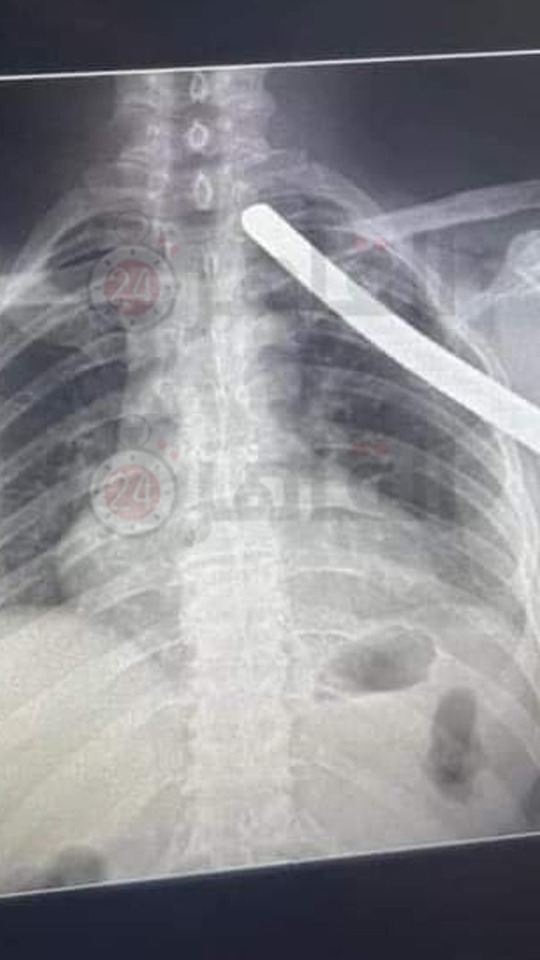

دخل في صدره سيخ وخرج الناحية التانية.. إنقاذ حياة عامل بناء بقصر العيني بعد جراحة دقيقة

استقبل قسم طوارئ قصر العيني التابع لمستشفيات جامعة القاهرة، حالة خطرة لعامل بناء أصيب بدخول سيخ حديد في صدره حتى خرج من الناحية الأخرى، الأمر الذي طلب تدخلا جراحيا من فريق الأطباء.

وأجرى أطباء قصر العيني، عملية جراحية باستخراج السيخ الحديد من جسد عامل البناء، بعد مروره من صدره ما بين القلب والرئتين والشراين الرئوية وأضخم شرايين الجسم الأورطي.

ونجح فريق أطباء قصر العيني، في استخراج سيخ الحديد من صدر عامل البناء، ما أدى إلى إنقاذ حياته وتحويله إلى قسم الرعاية بمستشفى قصر العيني.